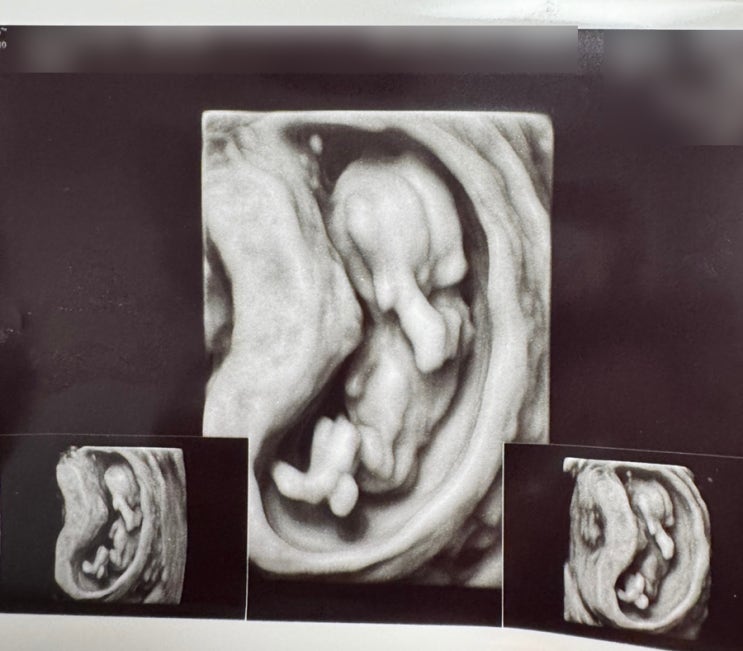

[임신일기] 12주차 정밀초음파 검사/ 통합검사/ 기형아선별검사/ 서울미즈병원

지난 9주차 이후 3주만에 검진 다녀왔습니다! 시간이 정말 안가요ㅎㅎㅎ 12주1일차 처음으로 정밀초음파를 ...